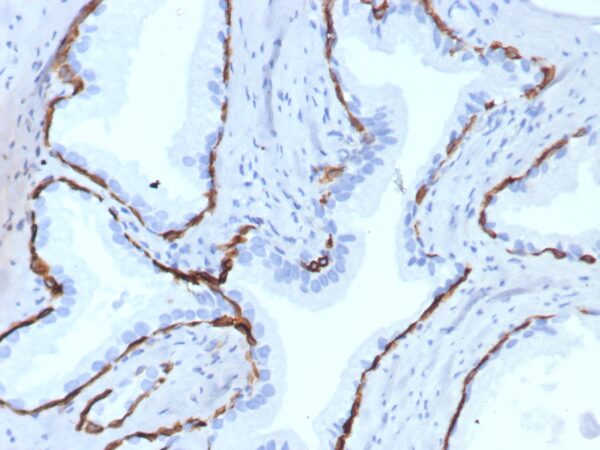

Formalin-fixed, paraffin-embedded human prostate stained with Cytokeratin 14 Recombinant Rabbit Monoclonal Antibody (KRT14/7977R). Inset: PBS instead of primary antibody; secondary only negative control.